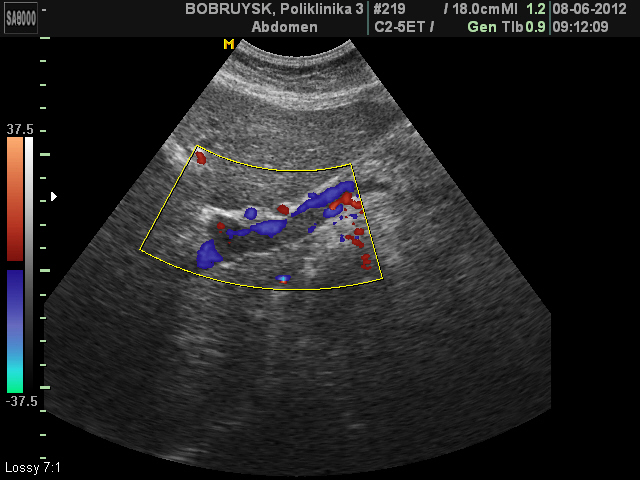

Женщина 62 лет.

Наблюдалась и лечилась в Минске, заключение подтверждено ангиографией там же.

Выписана под амбулаторное наблюдение и ленение по месту жительства, рекомендовано УЗИ в динамике.

Неполный тромбоз воротной вены и ее ветвей

Причин данного тромбоза не знаю, т.к пациентка пришла только с предыдущим УЗИ и результатами ангиографии с Минска.

Ни карточки ни выписки на руках не было.

Сослов пациентки, проходит амбулаторное лечение тромболитиками, рекомендовано УЗИ в динамике, по месту жительства и консультации по графику в Минске.